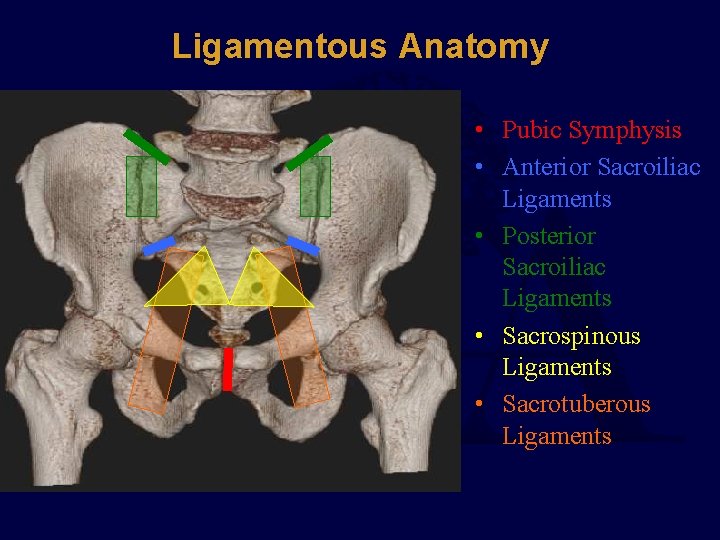

Ligamentous Anatomy • Pubic Symphysis • Anterior Sacroiliac Ligaments • Posterior Sacroiliac Ligaments • Sacrospinous Ligaments • Sacrotuberous Ligaments